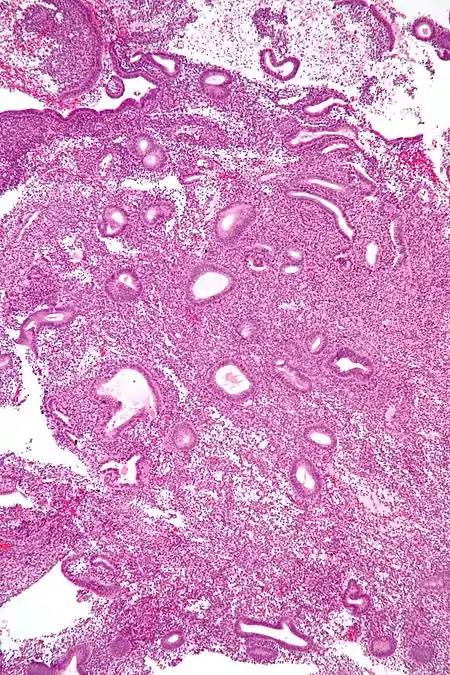

The endometrial biopsy is a medical procedure that involves taking a tissue sample of the lining of the uterus. The tissue subsequently undergoes a histologic evaluation which aids the physician in forming a diagnosis.

6. The tissue will be sent to a laboratory, where it will be processed and tested. It will then be read microscopically by a pathologist who will provide a histologic diagnosis.[4]